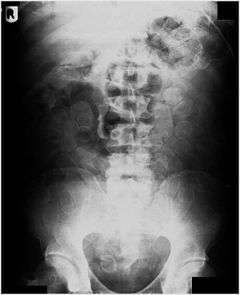

Plain radiograph of the abdomen of a drug "mule" showing drug capsules

Abdominal X-ray showing swallowed packages of cocaine.

This is often done using a mule's gastrointestinal tract or other body cavities as containers. Swallowing has been used for the transportation of heroin,[1][3][4] cocaine,[5] and MDMA/Ecstasy.[6] A swallower typically fills tiny balloons with small quantities of a drug. The balloons may be made with multilayered condoms, fingers of latex gloves,[5] or more sophisticated hollow pellets. One smuggling method involves swallowing the balloons, which are recovered later from the excreted feces. Alternately, the balloons may be hidden in other natural or artificial body cavities – such as rectum,[5] colostomy,[7] vagina, and mouth[8] – although this method is far more vulnerable to body cavity searches. A drug mule may swallow dozens upon dozens of balloons.[4] The swallower then attempts to cross international borders, excrete the balloons, and sell the drugs.

Routine detection of the smuggled packets is extremely difficult, and many cases come to light because a packet has ruptured or because of intestinal obstruction. Unruptured packets may sometimes be detected by rectal or vaginal examination, but the only reliable way is by X-ray of the abdomen. Hashish appears denser than stool, cocaine is approximately the same density as stool, while heroin looks like air.[10]